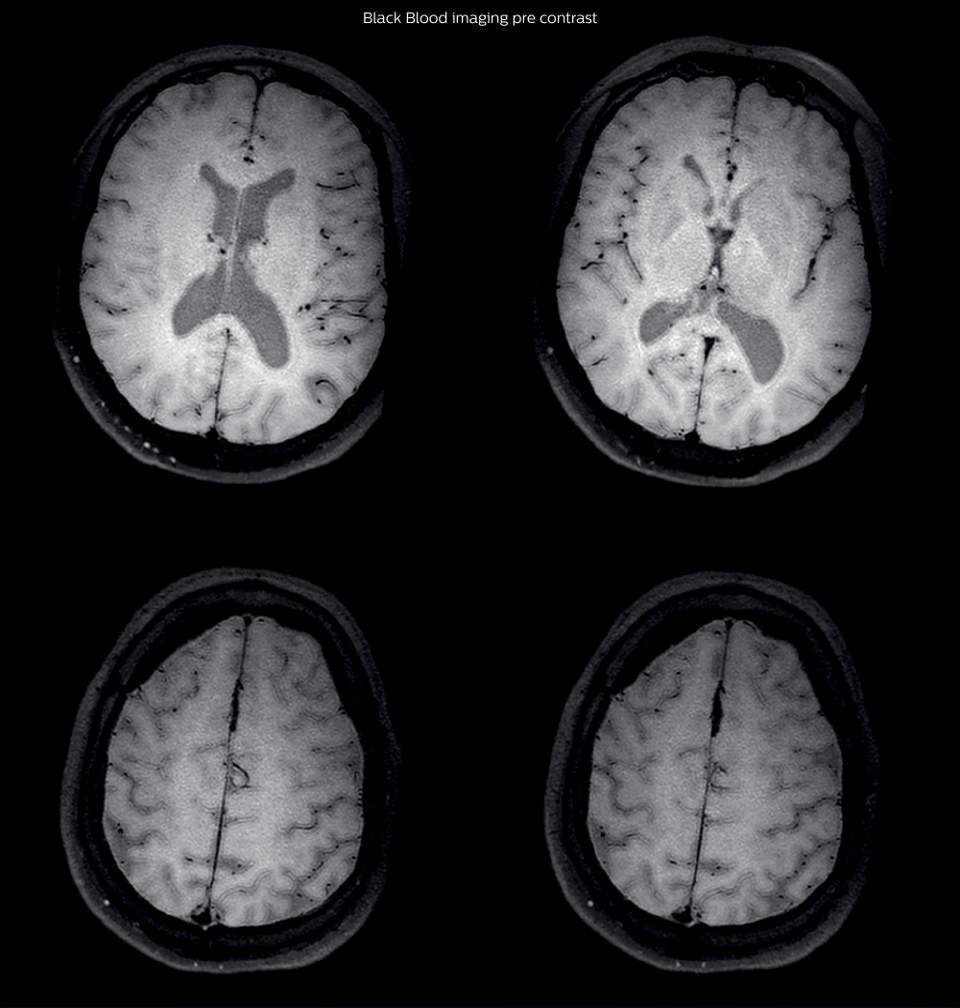

After a conventional routine MR imaging examination, the suspicion of vasculitis arose, therefore we performed an MRI including Black Blood imaging in a separate session. The dedicated ExamCard includes diffusion, FLAIR, MR angiography using TOF, and 3D T1 MRA with bolus injection. This ExamCard also includes Black Blood imaging before and after contrast. This examination was performed on our Ingenia 3.0T. Black Blood scan time 4:39 min, acquired voxel size 0.75 x 0.75 x 1.0 mm, 21 slices.

On FLAIR images we can see some nonspecific high signal abnormalities in frontal white matter bilaterally. On DWI we can see acute ischemic lesions which appear with high signal intensity. Arrows show vessel wall enhancement which appears concentric and homogeneous in different cerebral territories.